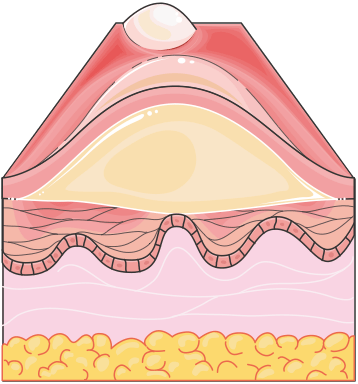

Second-Degree Burns: These burns extend into the dermis and are subdivided into:

- Superficial second-degree burns: Involve the upper layer of the dermis, characterized by blistering, intense pain, and moist, red wounds. Healing usually occurs within 10 to 14 days, with minimal scarring.

- Deep second-degree burns: Penetrate deeper into the dermis, causing more extensive damage. These burns are less painful due to nerve damage and may take 3 to 8 weeks to heal, often leaving scars or requiring skin grafts.

Figure 1.22, generated using Servier Medical Art, provided by Servier, licensed under a Creative Commons Attribution 4.0 unported license